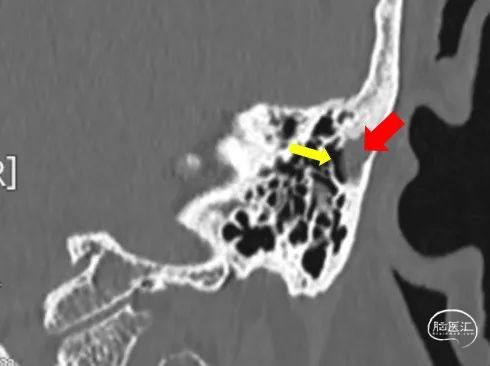

➤CT

乙状窦憩室

静脉窦狭窄

搏动性耳鸣是“血管性耳鸣”最常见的临床特征。静脉窦憩室形成或者静脉窦狭窄是主要的病因。通过门诊的CT和MR检查就能够明确诊断,初步筛选出需要外科干预治疗的患者。